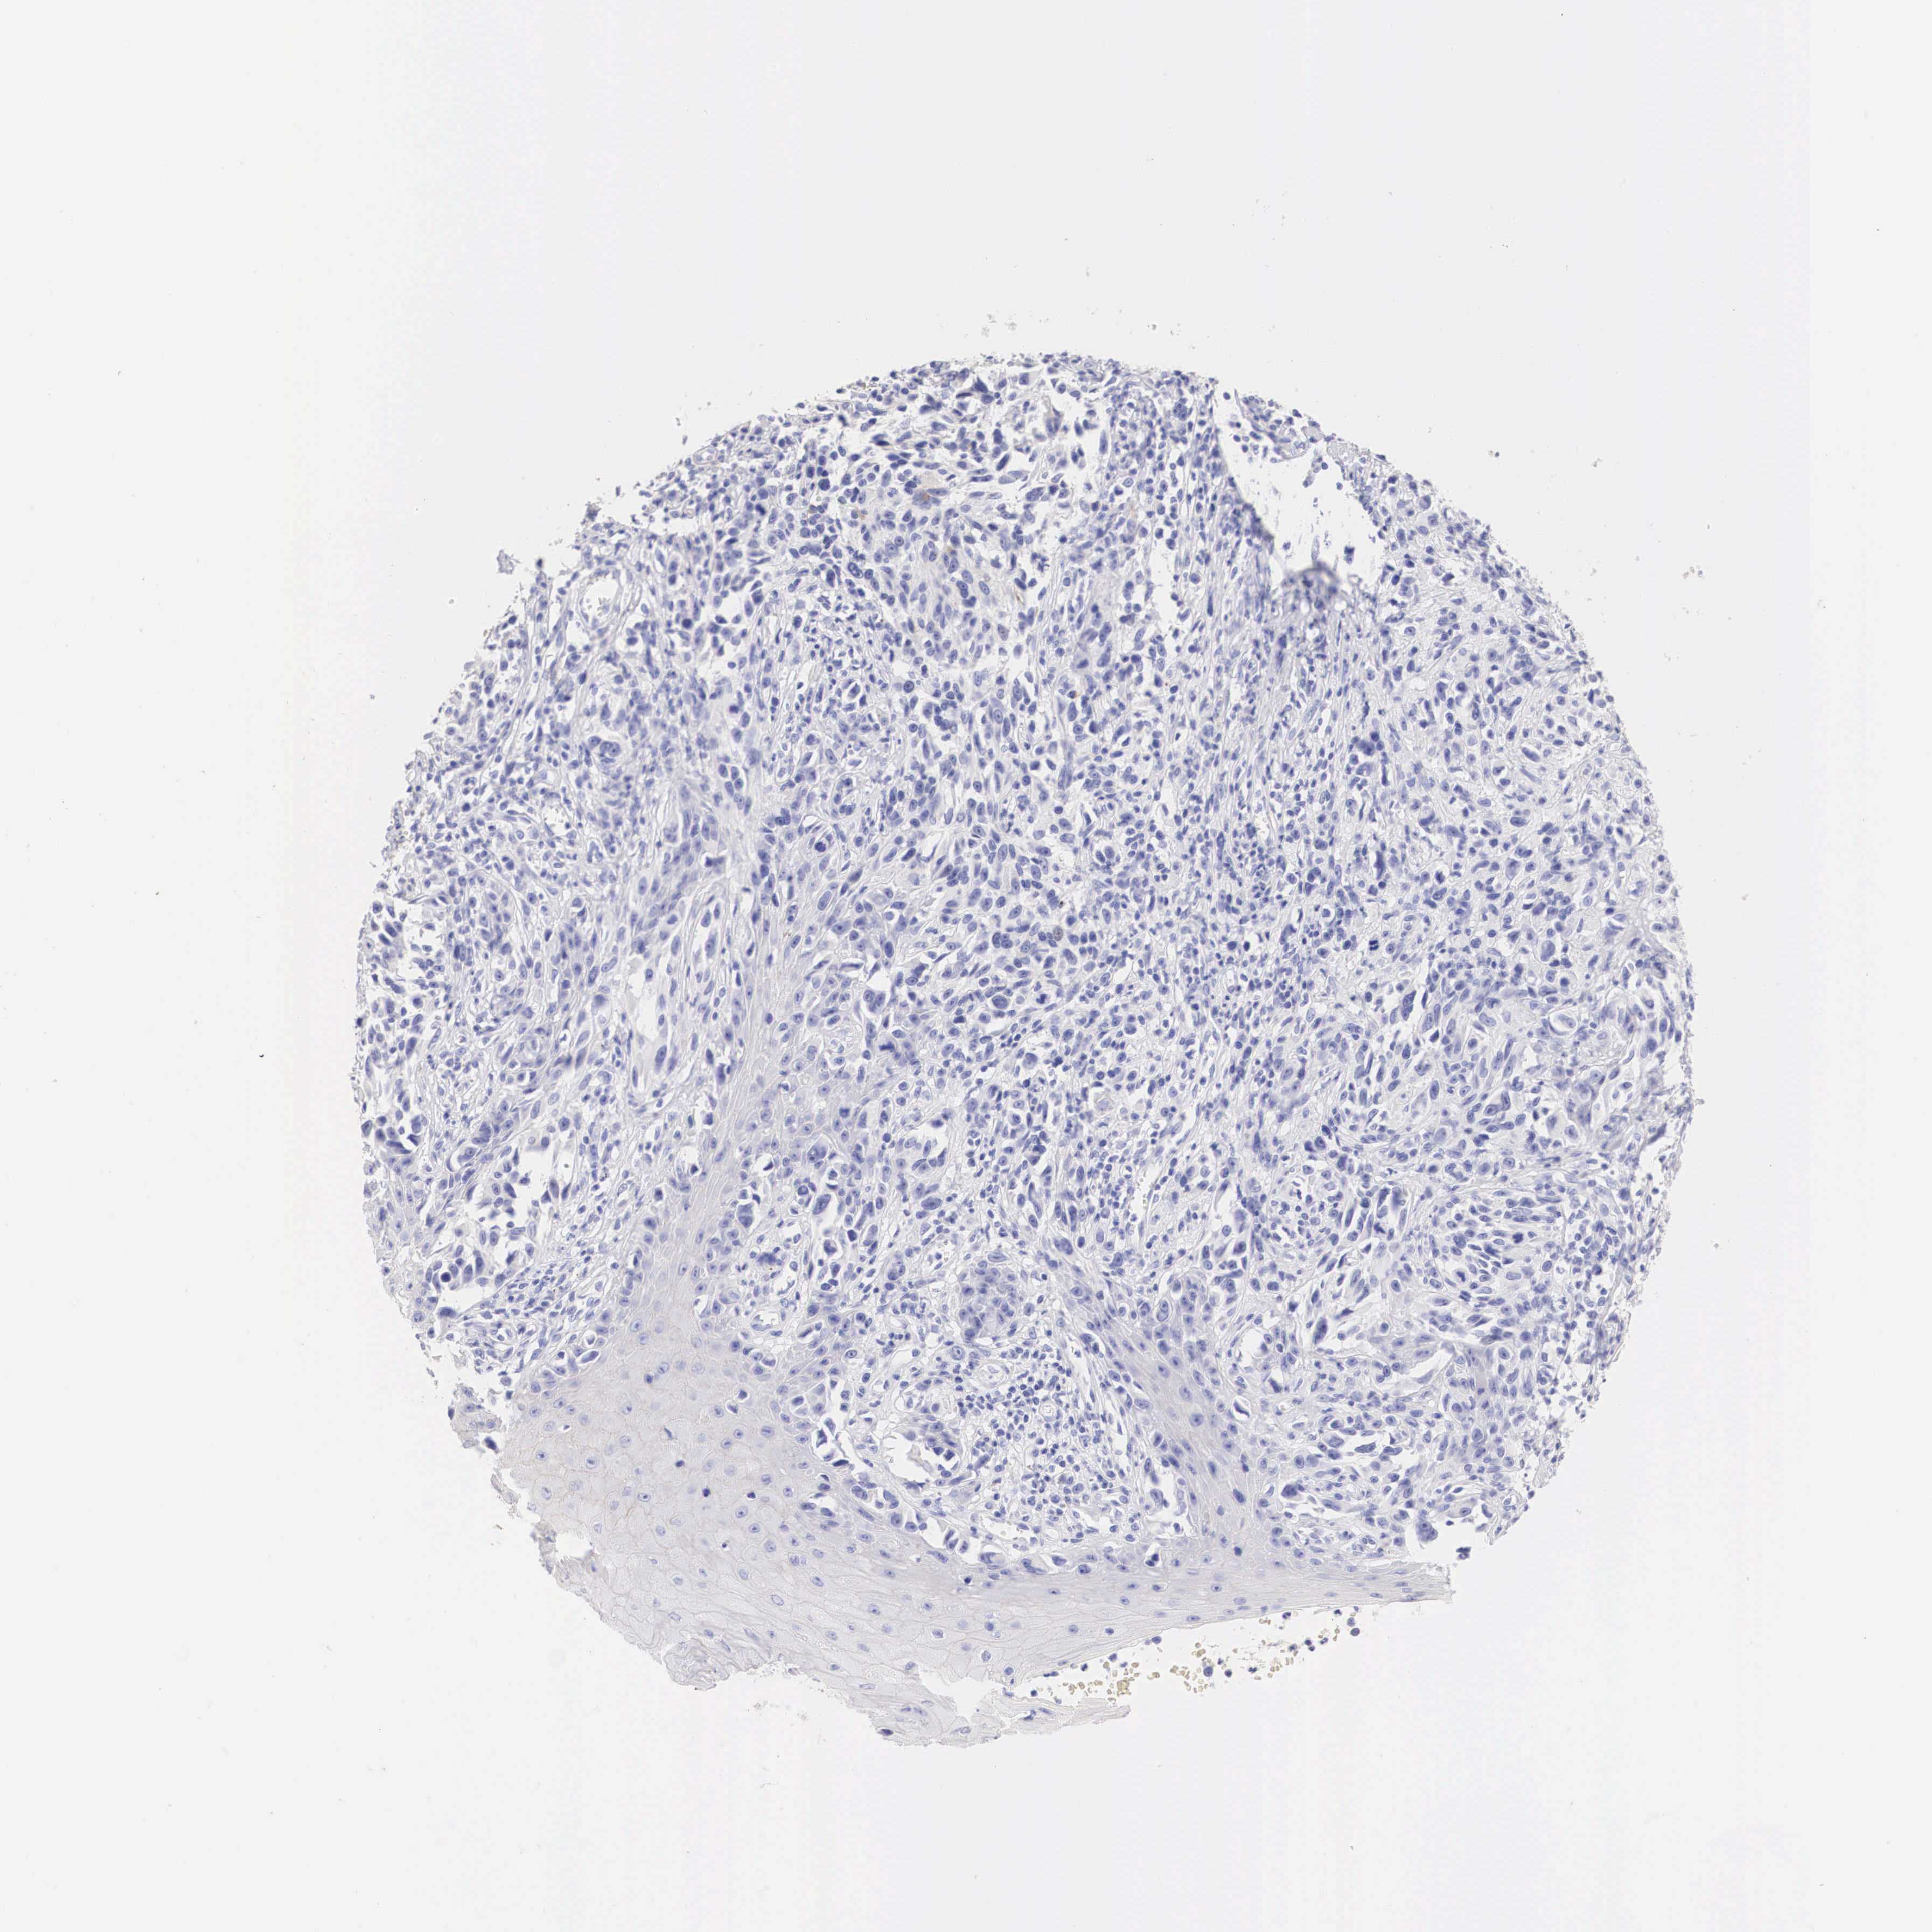

MELANOMA - Protein expressioni

A mouse-over function shows sample information and annotation data. Click on an image to view it in a full screen mode. Samples can be filtered based on level of antibody staining by selecting one or several of the following categories: high, medium, low and not detected. The assay and annotation is described here.

Note that samples used for immunohistochemistry by the Human Protein Atlas do not correspond to samples in the TCGA dataset.

Antibody stainingi

Antibody staining in the annotated cell types in the current human tissue is reported as not detected, low, medium, or high, based on conventional immunohistochemistry profiling in selected tissues. This score is based on the combination of the staining intensity and fraction of stained cells.

Each image is clickable and will lead to virtual microscopy that enables deeper exploration of all samples and also displays staining intensity scores, fraction scores and subcellular localization as well as patient and tissue information for each sample.

Antibody HPA001383

Antibody CAB000043

Antibody CAB020416

Antibody CAB062555

Malignant melanoma, NOS

Malignant melanoma, Metastatic site